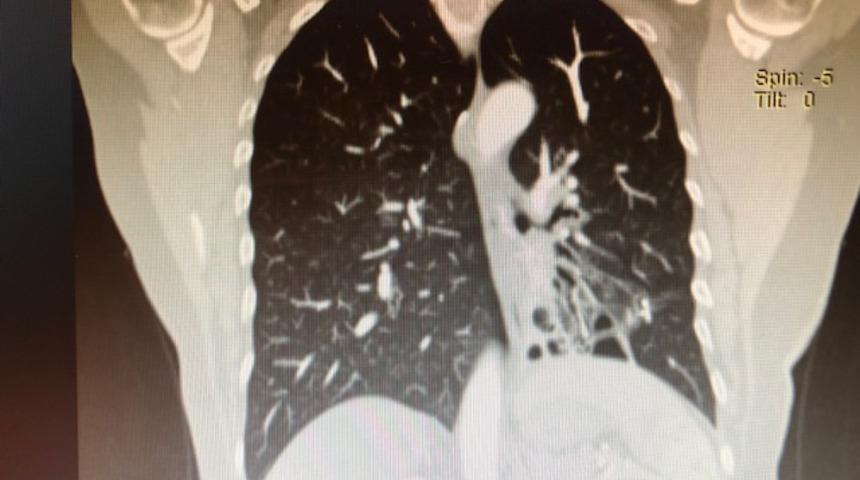

Konu ile ilgili bilgi veren Göğüs Cerrahisi Uzmanı Doç. Dr. Özkan Demirhan,” Soluk borusunun devamında ana bronş ve sonrasında bronşlar gelmektedir, bronş duvarının kas ve elastik yapısının bütünlüğünün bozulması sonucunda anormal ve kalıcı genişlemeye Bronşektazi denir. Bronşektazi doğumsal nedenlerden kaynaklanabileceği gibi sonradan da oluşabilir. Doğumsal nedenlerden kaynaklı Bronşektazi’de anatomik bozukluklar, damarsal bozuklular, solumun yolu üzerindeki silia tabakası bozuklukları ve immün sistem zayıflıkları rol oynar. Sonradan gelişen Bronşektazi’de ise sigaranın olumsuz etkilerinin yanı sıra sık geçirilen akciğer enfeksiyonları, bronşu tıkayan (yabancı cisim), bronşu daraltan durumlar ( bronş etrafında bulunan lenf bezelerinin bası yapması), aspirasyon pnömonisi gibi durumlar söz konusu olabilir. Bronşektazi en sık sol alt lobda görülmesine rağmen akciğerin tüm bronşlarını etkileyebilir” dedi.

Bronşektazi’nin tedavi şekline değinen Demirhan,” Bronşektazi hastaları önce göğüs hastalıkları uzmanına gidiyor. Uzun süre tedavi ediliyor. Rutin tedavi prosedürü de budur. Önce medikal tedavi olmuyorsa ameliyat düşünülür. Eğer medikal tedavilerde enfeksiyon dirençli hale geldi ve kurutmak imkansız ise bu durum da hastanın yaşam konforunu bozuyorsa ameliyat devreye girer. Yaygın Bronşektazi’lerde ameliyat önerilmiyor, Bronşektazi sınırlı yani lokalize ise daha iyi sonuç alınıyor. Cerrahide lokalize Bronşektazi hastalarına kapalı yöntemlerle videotorokoskopik veya robotik ameliyatlar yapıyoruz. Bu ameliyatlardan sonra hasta önemli ölçüde sağlığına kavuşabiliyor. Eğer hastalar ihmal eder ya da ameliyat gerektiren durumları geciktirirlerse enfeksiyon vücuda dağılıp apse gelişimine, Ampiyem’e, hemoptiziye (balgamdan kan gelmesine ), beyin apsesine ya da nadir de olsa sepsise neden olabilir” ifadelerini kullandı.